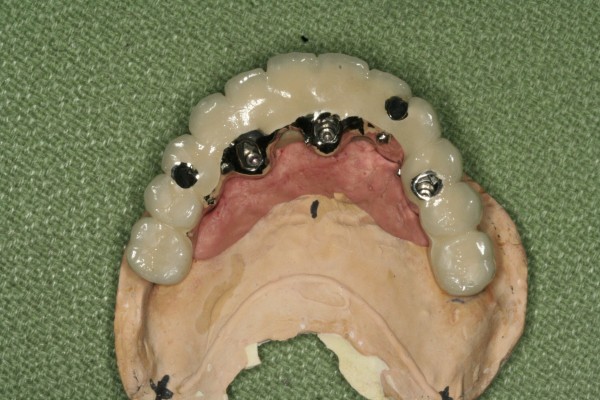

Milling bar 5 milling bar가 불편한 fixed implant bridge